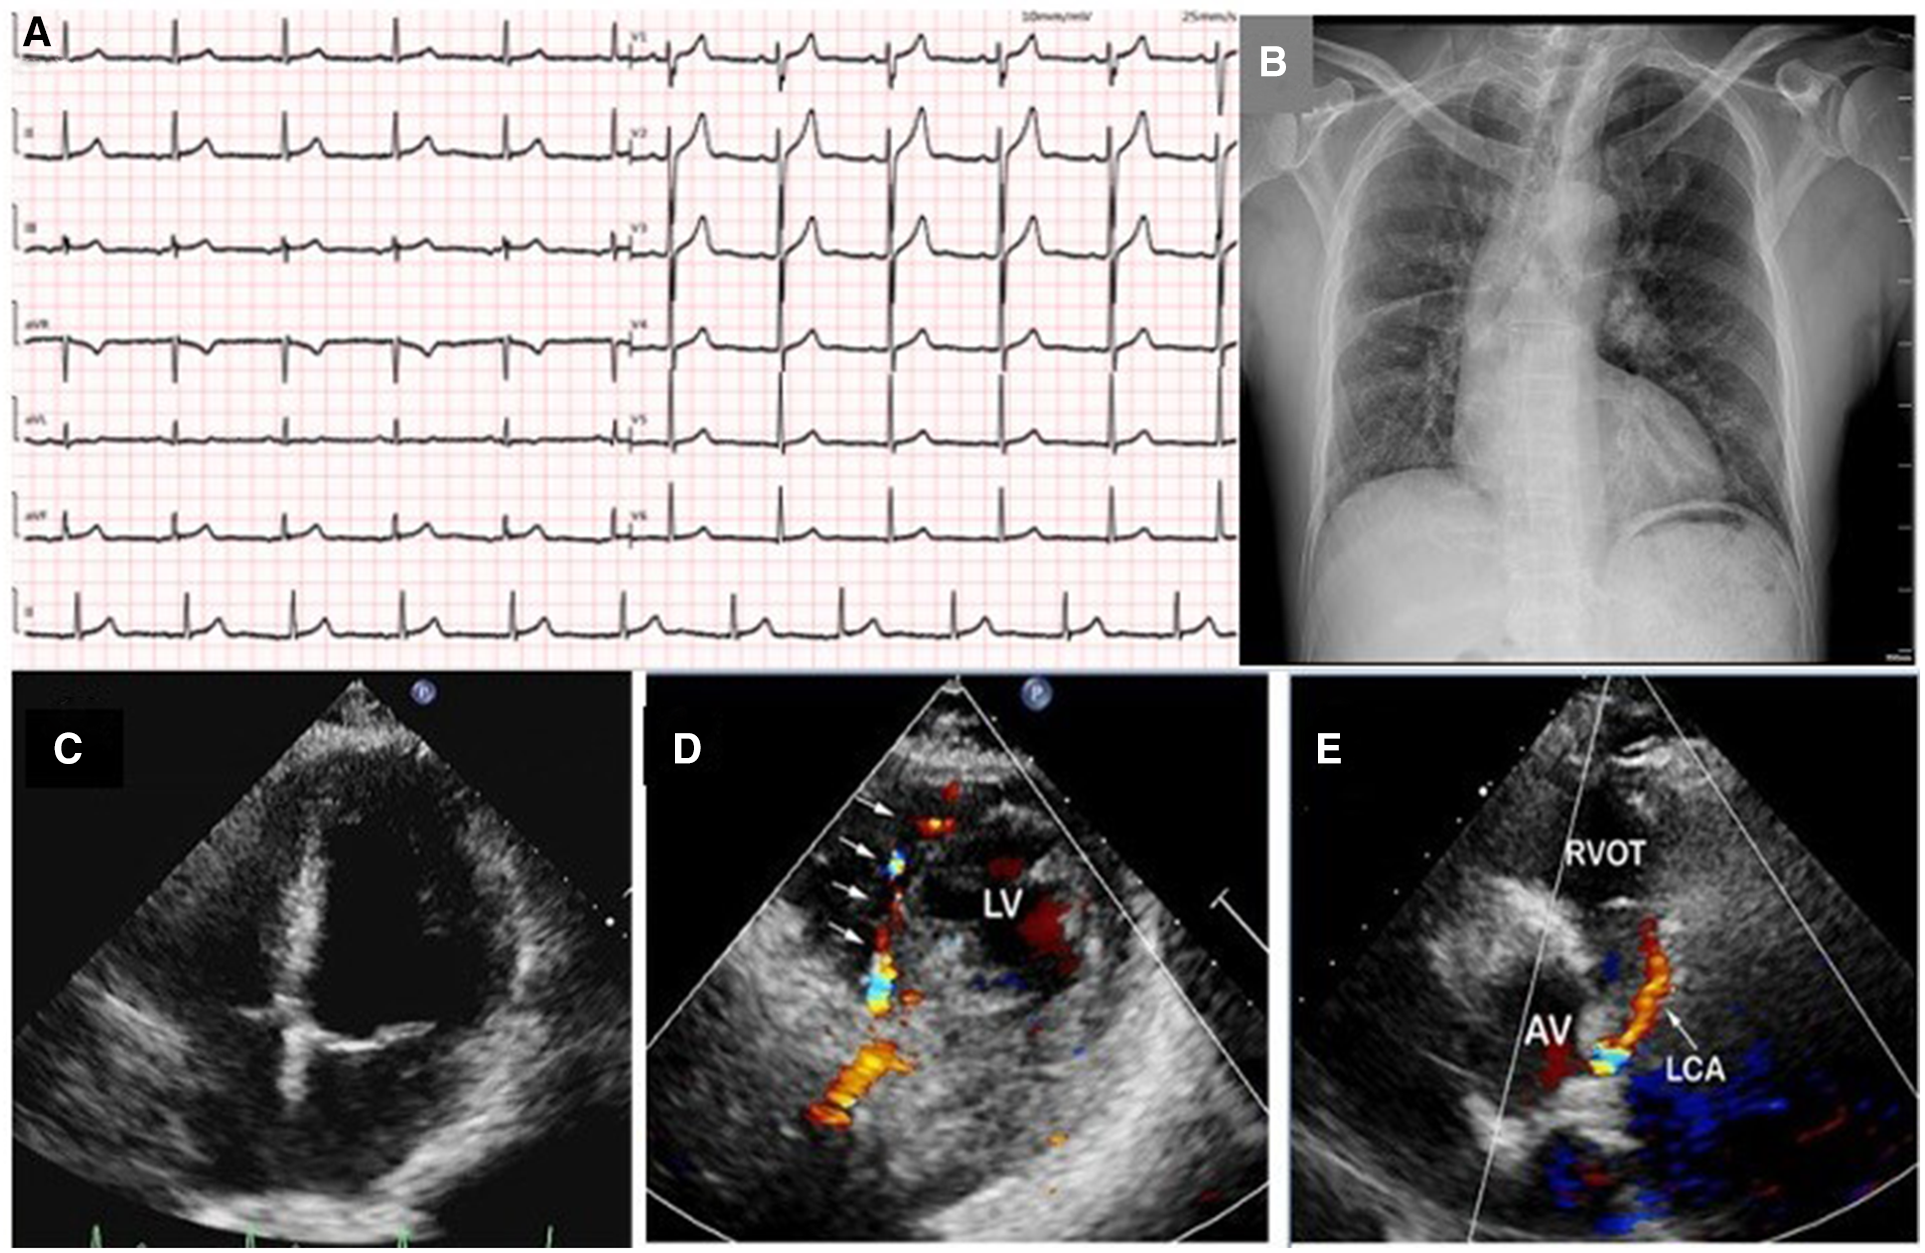

A 49-year-old man with no previous medical history presented to our hospital with complaint of chest pain, palpitations, and diaphoresis during exercise for 3 months. The chest pain was able to be relieved by rest and nitrates. Upon admission, physical examination revealed normal range of blood pressure (135/74 mmHg), heart rate (78 beats/min), respiratory rate (18/min), and oxygen saturation level was 99% (room air). He denied history of hypertension, diabetes, and family history of heart diseases. Personal habits included smoking (half pack/day) and drinking. Cardiac and pulmonary examination revealed normal heart sounds without murmurs and clear lungs. Laboratory tests indicated that complete blood count with differential, comprehensive metabolic panel, renal function, troponin, N terminal pro-brain natriuretic peptide (NT-proBNP), and several tumor markers were within normal limit. A 12-lead ECG illustrated normal sinus rhythm without ST-segment and T-wave changes (Figure 1A). Chest x-ray showed scoliosis, cardiac enlargement, and briefly normal vascular markings on both sides, along with a rightward mediastinal shift (Figure 1B).

Figure 1

A 12-lead ECG illustrated normal sinus rhythm without ST-segment and T-wave changes (A); chest x-ray showed scoliosis, cardiac enlargement and briefly normal vascular markings on both sides, along with rightward mediastinal shift (B); transthoracic echocardiography revealed normal size of four chambers, left ventricular, and valvular function (C); color Doppler in parasternal short-axis view showed abundant collateral blood signals within the ventricular septum (D); an abnormal continuous blood flow directed into the pulmonary artery was also observed (E). LV, left ventrium; RVOT, right ventricular outflow tract; AV, aortic valve; LCA, left coronary artery.

TTE revealed normal size of chambers and left ventricular systolic function with left ventricular ejection fraction 60%. No abnormal wall motion and valvular regurgitation were observed. However, multivessel myocardial collateral blood flow signals at the left ventricular wall and ventricular septum were observed by color Doppler flow imaging (CDFI). At parasternal short-axis view, a red shunting flow seemingly from the left coronary artery (LCA) into the pulmonary artery (PA) was seen by CDFI, and a continuous shunt following the path of this vessel, which appeared as low velocity with pronounced diastolic phase on pulsed Doppler was also detected (Figures 1C–E and Supplementary Videos S1A,S1B). The ostiums of the left and right coronary artery (RCA) were not clearly visualized with TTE in this patient. At the same time, the main pulmonary artery exhibits normal blood flow and pressure.